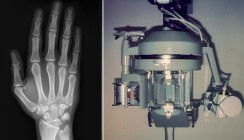

Die erste Ausgabe des Implantologie Journal 2026 ist erschienen und steht ganz im Zeichen von Fortschritt und Zukunftsperspektiven. Unter dem Leitthema „State of the Art und Ausblick“ beleuchtet das Heft ein ebenso spannendes wie dynamisches Forschungs- und Praxisfeld der modernen Implantologie.

Im klinischen Teil geben Dr. Georg Bach, Präsident der DGZI, und Markus Bach ein fundiertes Update zu bildgebenden Verfahren in der Zahnmedizin. Dr. Dr. Florian Bauer stellt anhand eines praxisnahen Fallbeispiels das Miesbacher Konzept zur Sofortimplantation vor, während Dr. Daniel Schulz die Entscheidungsfreiheit im digitalen Workflow praxisorientiert beleuchtet.